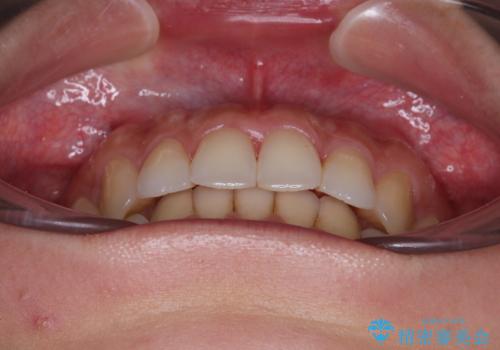

捻れた前歯をインビザラインで整える

- 捻れた前歯が飛び出しており、口が閉じにくいとのことで来院された患者様です。

出っ歯というわけではないものの、前歯の捻転により口唇が押し出されている状態でした。

親知らずを抜去し、歯列全体を後方に移動させつつ、IPR(歯と歯の間を削る)でスペースを獲得し、インビザラインを用いて叢生を解消しながら前歯の突出を改善することとしました。

骨格的に上下正中がずれていたため、奥歯がしっかりと噛み合うか心配でしたが、ずれているなりに、しっかりとした咬み合わせとなりました。